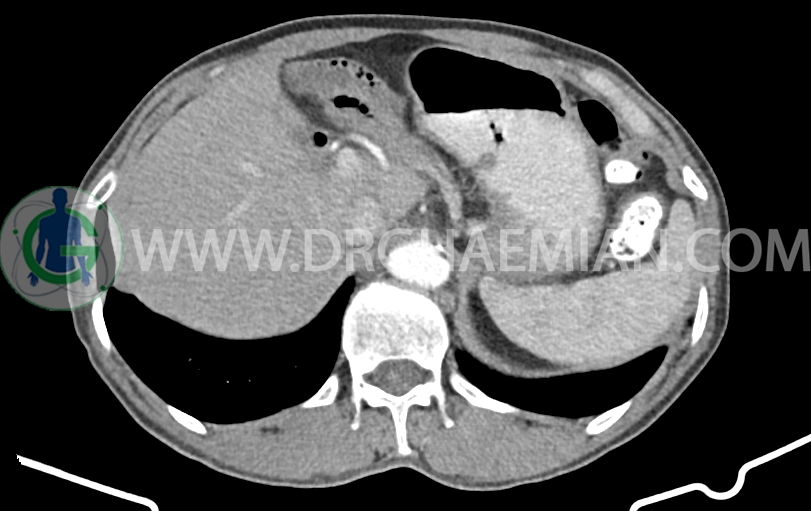

کانون کلسیفیه کوچک فاقد اهمیت بالینی در لوب راست کبد رویت شد

پنوموبینی در لوب چپ کبد مشهود است.

ضایعه ای در مجاری صفراوی، طحال، کلیه ها و آدرنالها مشهود نیست.